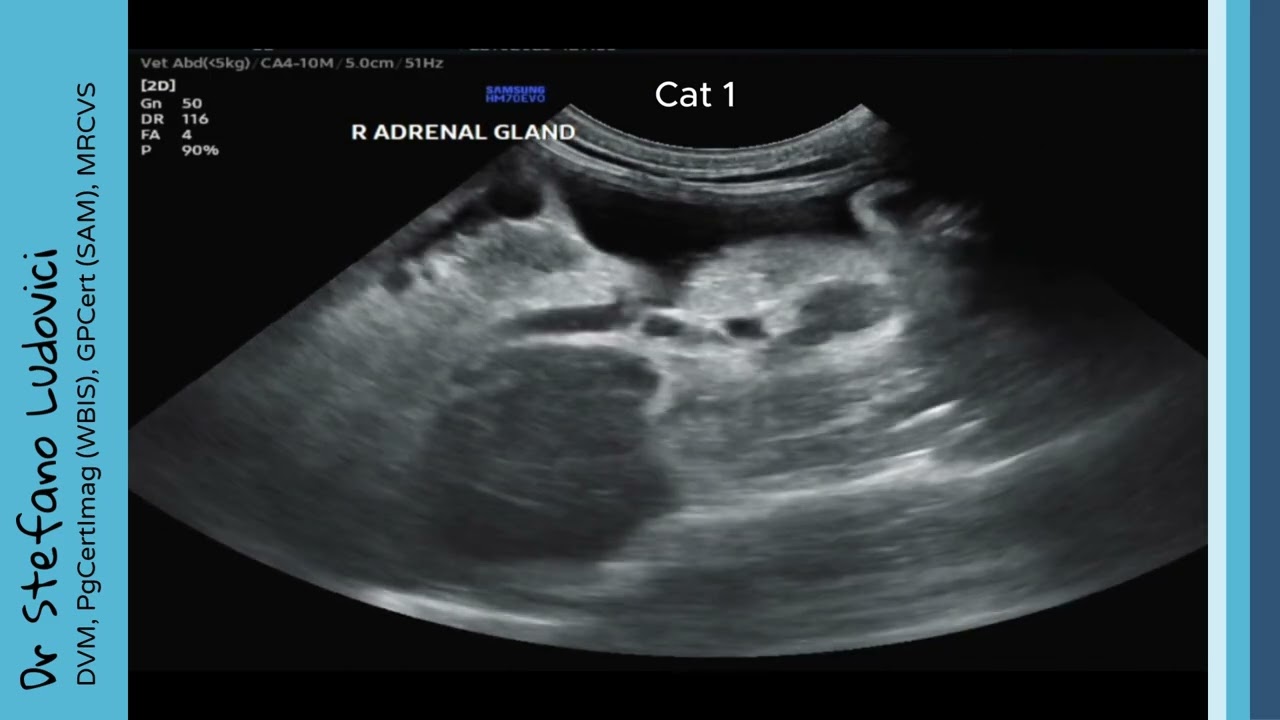

• How to Scan Feline Adrenal Glands | Left & Right Adrenal Ultrasound Tutorial

How to Scan Feline Adrenal Glands | Left & Right Adrenal Ultrasound Tutorial